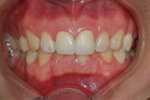

| ¾Õ´Ï ÃæÄ¡°¡ ÀÖ¾î¿ä |